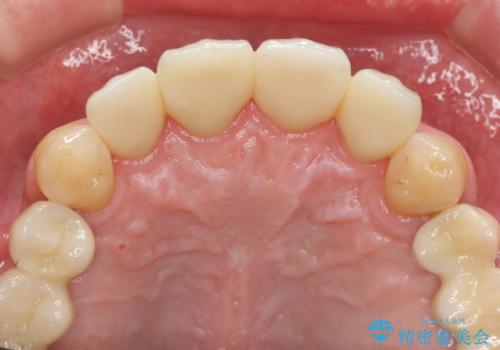

「 放置した虫歯 」 前歯セラミック治療

虫歯の放置により、根管治療や深い虫歯に対する処置が必要になりましたが丁寧に一つづつ処置を行ったことで抜歯をすることなく歯を残すことができました。

セラミッククラウンの製作をする前に、歯内・歯周環境の整備は非常に大切です。